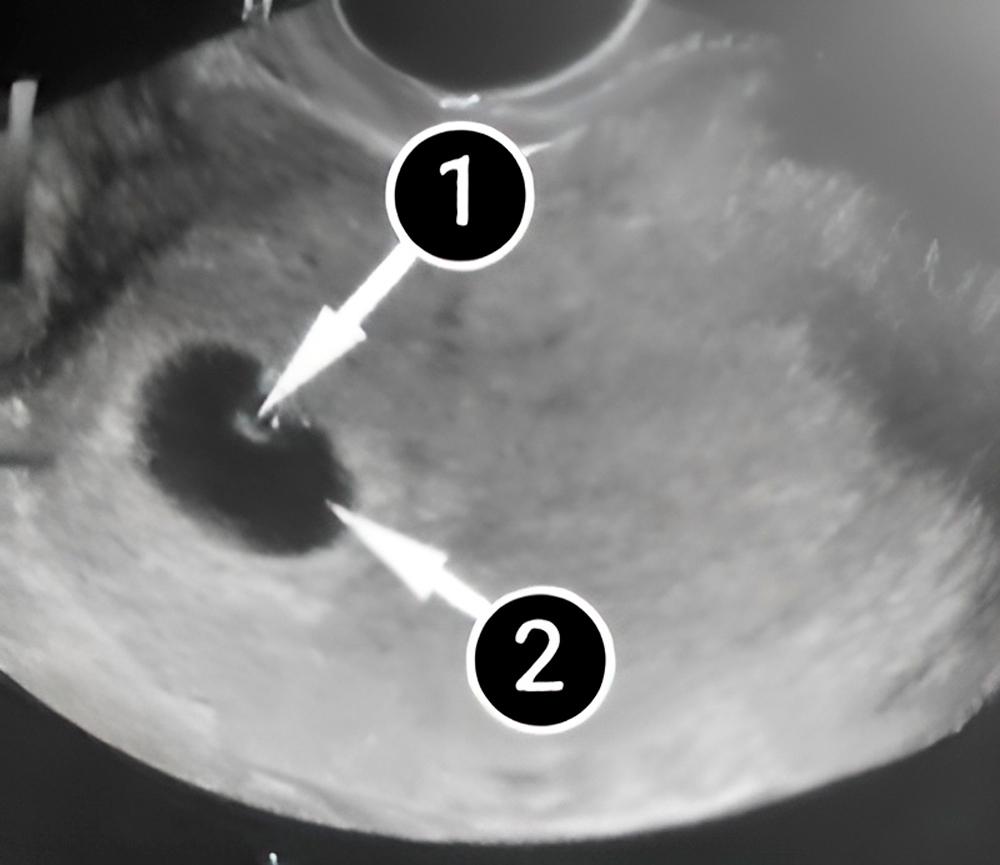

En la siguiente foto, se ve el saco amniótico, que se encuentra cerca de la pared derecha del útero. El embrión, que en esta imagen parece una pequeña semilla, está adherido a la pared del saco amniótico.

La forma del bebé es fácil de distinguir. Al lado del cuerpo del bebé se encuentra el saco vitelino, que le proporciona los nutrientes que necesita para crecer.

embrión

saco amniótico